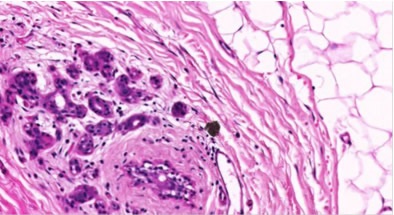

20X magnification of breast tissue specimen with 0.5μm resolution

Figure 2. 20X magnification of breast tissue specimen with 0.5μm resolution. Image credit: Huron Digital Pathology.

Researchers are making use of the TissueScope for developing 3D images of whole specimens from individual slides, to achieve a more thorough understanding of breast tissue. Overall, new imaging modalities can be more effectively validated using the Huron Digital Pathology’s TissueScope. It offers the sharp and clear imaging quality needed for detecting tumor heterogeneity, with up to 0.25μm/pixel resolution at 40x magnification. The instrument is unmatched in the versatility and efficiency it offers because it can simultaneously scan up to 12 brightfield slides in sizes ranging from 1” x 3” to 6” x 8” and image whole slides in minutes. Images can be very easily viewed and managed using the HuronViewer™ and TissueView™ software and workflow optimization can be improved by pairing with the TissueSnap™.